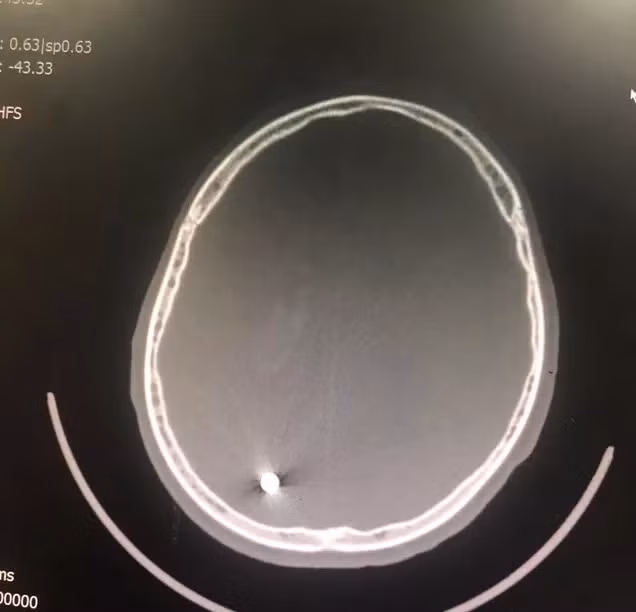

Phim chụp vết thương với viên đạn xuyên qua não bệnh nhân - Ảnh: Bác sĩ cung cấp

Kết quả chụp X-quang cho thấy vết thương nhỏ đường kính 0,55 mm xuyên qua não từ trán đến đỉnh chẩm bên phải. Vết thương xuyên dọc theo chiều dài não khiến thiếu niên 16 tuổi này bị liệt nửa người bên trái. Bệnh nhân được phẫu thuật làm sạch vết thương và lấy viên đạn trong não ngay sau đó.